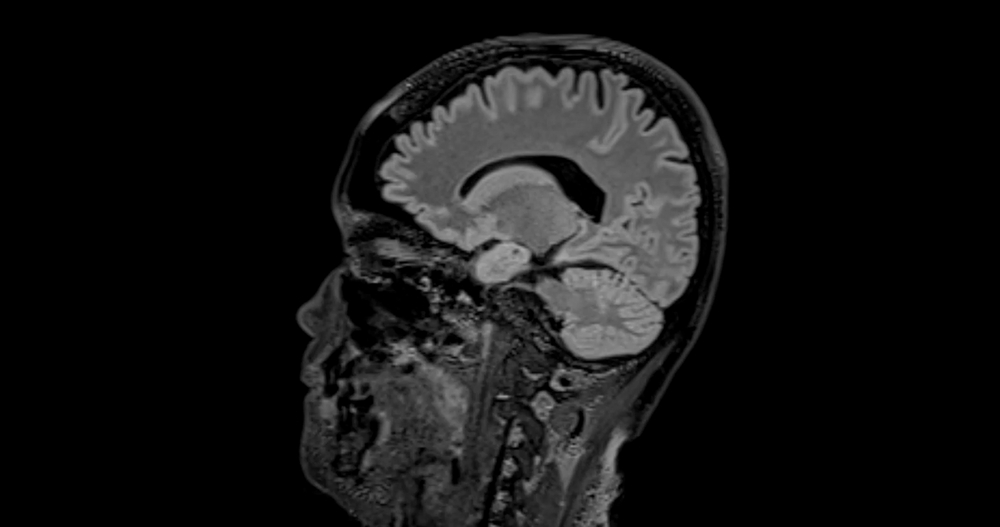

Dalis genetinių pakitimų veikia ir uoslę: normaliomis sąlygomis uoslės nervų ląstelės siunčia signalus uoslės svogūnėliui, tačiau sergant šiuo sindromu tie signalai smegenų nepasiekia, todėl žmogus nejaučia kvapų. Jeigu šio pojūčio netrūksta, būklė vadinama normosminiu idiopatiniu hipogonadotropiniu hipogonadizmu.